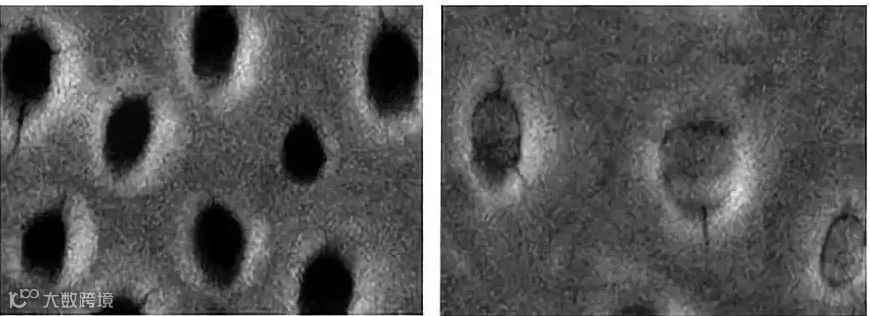

(图左为使用前:暴露的牙小管 图右为使用后:暴露的牙小管得到封堵)

BESMOON牙膏采用搪瓷技术,在刷牙的过程当中,牙齿表面形成类羟基磷灰石层,成分接近于牙齿的天然成分,阻断外界的致敏源。

同时有效成分还能深入渗透,直接作用于牙本质小管的神经末梢,降低神经兴奋性,